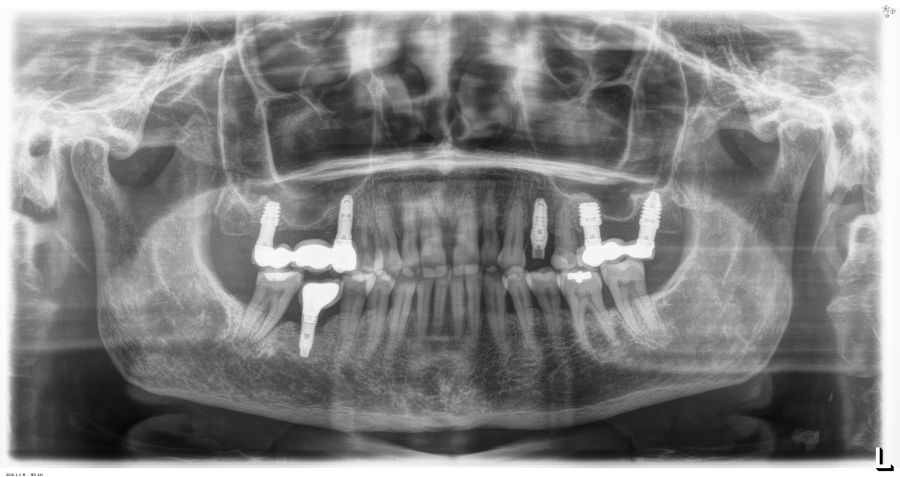

En cuanto a la rehabilitación protésica, en todos los casos se utilizó una prótesis atornillada con transepitelial para prótesis unitaria. La supervivencia de las prótesis fue del 100%, sin encontrarse fracaso en ninguna de ellas al igual que los implantes, con un tiempo de seguimiento de tres años. Durante el primer año, en las visitas de control, ninguno de los implantes mostró sangrado al sondaje ni inflamación de los tejidos periimplantarios. La media de la pérdida ósea en este punto fue de 0,32 mm (+/- 0,60) y la media de la pérdida ósea distal de 0,31 (+/- 0,48). A los dos años, no se registraron tampoco signos inflamatorios en ninguno de los implantes y la pérdida ósea mesial del conjunto fue de media de 0,38 mm (+- 0,54) y la distal de 0,64 mm (+/- 0,70). En la última visita a los 3 años, los tejidos periimplantarios siguieron estables, sin signos de inflamación y la media de la pérdida ósea mesial fue de 0,40 mm (+/- 0,53) y la distal de 0,69 (+/- 0,55) (Figura 5). En las Figuras 6-12 se muestra uno de los casos incluidos en el estudio.